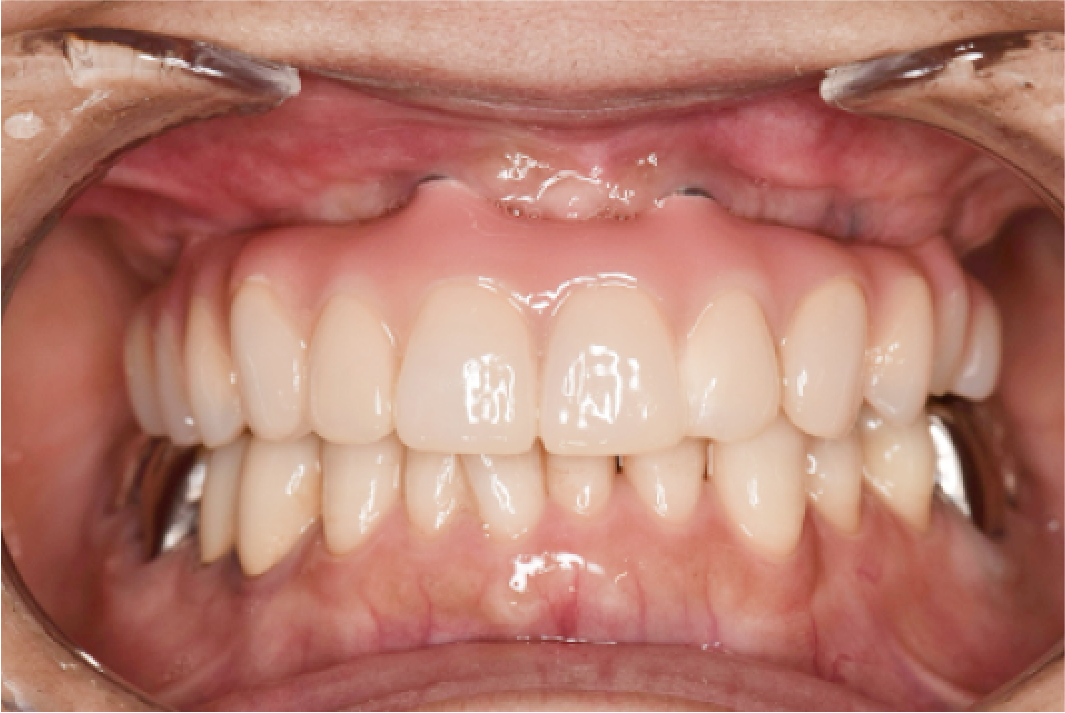

CASE04

■ 治療内容

上下顎All-on-4インプラント治療

■ 治療費用

6,627,000円(税込)

■ 治療期間

約9ヶ月

■ リスク

治療後の腫れや出血、またメンテナンスを怠ることで周囲炎のリスクあります。